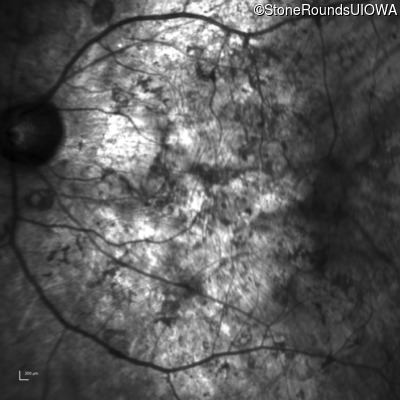

Age at visit: 33 years

OD OS